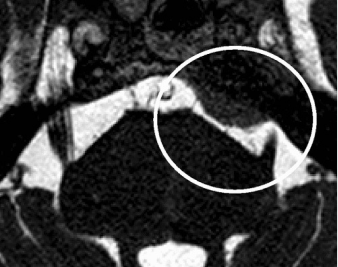

Though primarily a clinical diagnosis, Magnetic resonance imaging (MRI) imaging can detect changes in trigeminal root, any neuromuscular compression and to rule out secondary pathology. MRI can diagnose entire course of nerve, root atrophy, and CPA cistern. 3D fast imaging employing steady-state acquisition(FIESTA) and contrast-enhanced 3D time-of-flight (TOF) magnetic resonance angiography (MRA) in combination with unenhanced MRA are becoming popular in detecting the vessel involved and in detecting the vascular conflict.